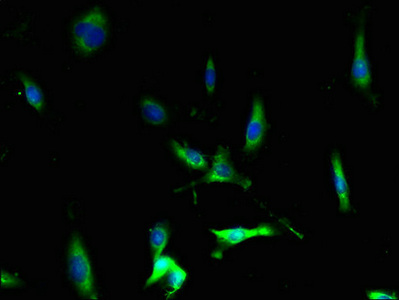

Immunofluorescent analysis of U251 cells using CSB-PA004839LA01HU at dilution of 1:100 and Alexa Fluor 488-congugated AffiniPure Goat Anti-Rabbit IgG(H+L)